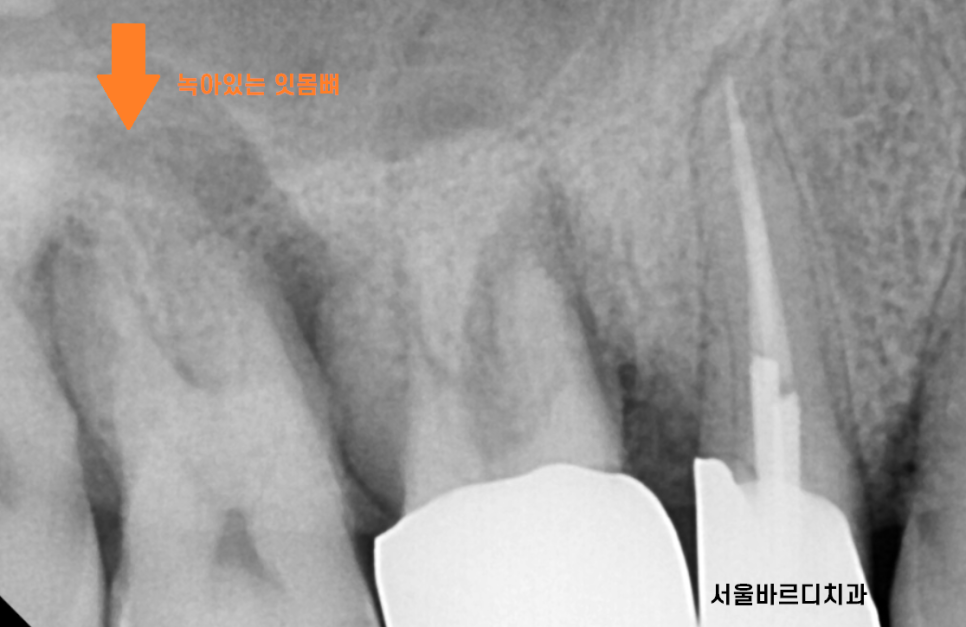

역시나 잇몸뼈가 머리까지 차 있어야하는데

많이 내려가 있는것이 보입니다.

유독 안좋아보이는 오른쪽 윗니 치아

추가적으로 검사를 해보았는데요.

큰 어금니 2개 상태가 영 ㅠㅠ 별로네요.

잇몸뼈가 많이 내려가다보니

어금니 시림 현상이 발생

해결하기 위해서는

2가지 방법이 있습니다.

- 신경치료를 한다

-> 잇몸뼈가 짱짱할 때나 가능

- 뽑는다.

환자분은 치아가 흔들리고 있어서

방법이 없었습니다.